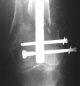

A new toy is more interesting and fashionable. And anyway it is not panacea, i have already seen presentations with LISS failures like the attached one presented by D.Seligson. And people also demonstrated incisions say that the method is not so LESS invasive as it supposed to be.